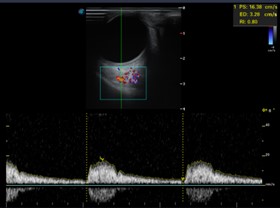

Imágenes C y D: las arterias ciliares, central de la retina flujos anterógrados normales, con espectrometría en parámetros normales (no hay alteración vascular).